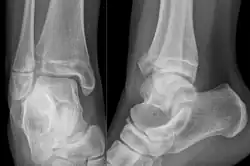

X-ray of a Tillaux fracture in an 11 year old female

A Tillaux fracture is a Salter–Harris type III fracture through the anterolateral aspect of the distal tibial epiphysis.[1] It occurs in older adolescents between the ages of 12 and 15 when the medial epiphysis had closed but before the lateral side has done so,[2] due to an avulsion of the anterior inferior tibiofibular ligament, at the opposite end to a Wagstaffe-Le Fort avulsion fracture